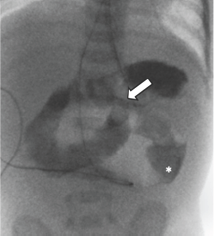

Upon arrival, an UGI study was performed as part of diagnostic work-up. Normal position of the duodenal jejunal junction (DJJ) was confirmed, and the level of obstruction appeared to be several centimeters distal from the ligament of Treitz (Figure 2). There was complete obstruction in the proximal jejunum with contrast material opacifying the dilated stomach, duodenum, and proximal jejunum. The appearance of the obstruction did not resemble a midgut volvulus. A nasogastric tube was in place to decompress the stomach and bowel proximal to the obstruction.

Figure 2: AP fluoroscopic view of an upper gastrointestinal study (UGI) shows normal position of the duodenojejunal junction (DJJ) and dilated proximal jejunum. Obstruction was several centimeters distal from the ligament of Treitz (*).